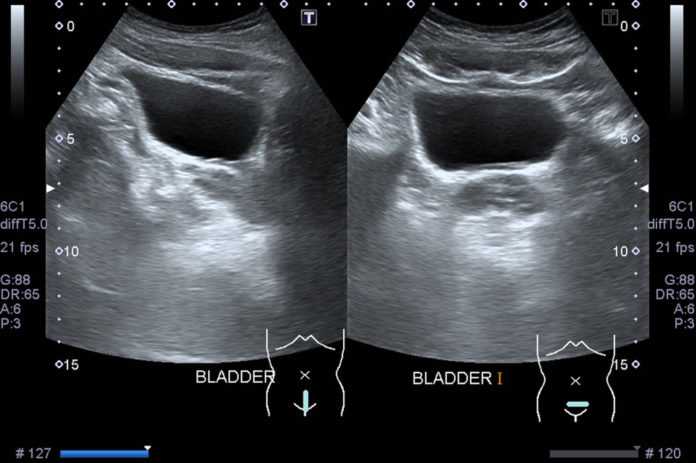

Мочевой пузырь – это полый мышечный орган, который хорошо диагностируется ультразвуковым методом при условии его наполнения.

Основными параметрами мочевого пузыря, несущими важную информацию для специалистов, являются:

- форма;

- размер (объем);

- структура;

- толщина и гладкость стенок;

- степень наполнения и опорожнения;

- характер содержимого пузыря;

- количество остаточной мочи.

Расшифровка этих показателей позволяет врачу оценить состояние мочевого пузыря и при тщательном анализе клинической картины поставить правильный диагноз.

Нормы по УЗИ мочевого пузыря

- зависит от уровня его наполненности и состояния окружающих органов. На поперечных снимках – это округлый орган, на продольных – яйцевидный. Контуры пузыря четкие и ровные. У женщин на форму пузыря влияет наличие беременности и количество родов. В отличие от мужского пузыря, женский более сдавлен сверху и расширен по бокам. Эти факторы обязательно учитываются при расшифровке УЗИ.

Структура

- в норме эхонегативная. Чем старше пациент, тем эхогенность выше (за счет хронических воспалительных заболеваний).

- средняя емкость мочевого пузыря у женщин 250-550 мл,

- у мужчин – 350-750 мл.

Стенки мочевого пузыря

- они по всей поверхности должны быть одинаковой толщины: от 2 до 4 мм (зависит от степени наполненности). Если в одном или нескольких участках наблюдается локальное утолщение/истончение стенки, то это явление рассматривается как патология.

Остаточная моча

- при УЗИ мочевого пузыря измеряется обязательно. В норме количество остаточной мочи не должно быть больше 50 мл.